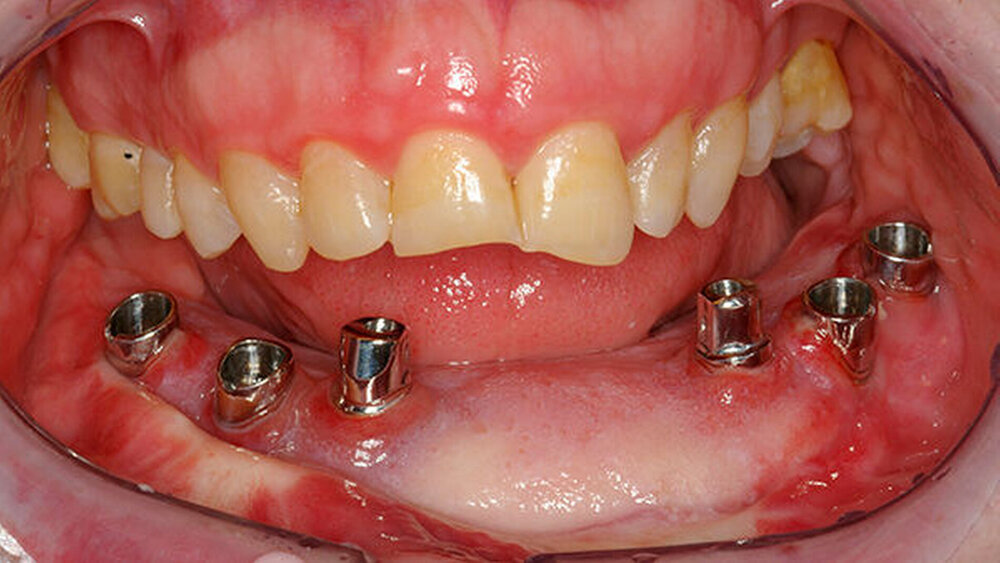

Das Verzeichnis bezieht sich in erster Linie auf Behandlungsorte, an denen intraorale defektprothetische Versorgungen durchgeführt werden. Falls auch extraorale Behandlungen durchgeführt werden, ist dies extra vermerkt. Für die Suche nach rein epithtetischen Behandlungsorten wird auf die Website desDeutschen Bundesverbandes der Epithetiker e.V.verwiesen.